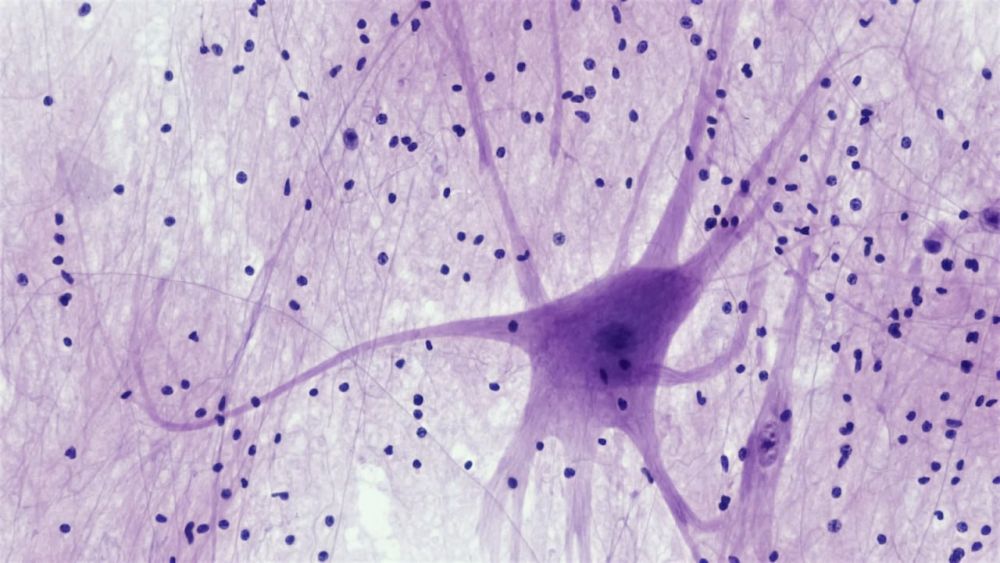

Трорилузол, новое экспериментальное лекарство от болезни Альцгеймера, обращает вспять потерю памяти и снижение когнитивных способностей у мышей, вмешиваясь на ранней стадии заболевания. В частности, он действует за счет снижения токсичных уровней глутамата (нейромедиатора), тем самым ограничивая гиперактивность синапсов — явление, которое, как известно, вызывает неврологические повреждения. Таким образом, этот препарат может стать потенциально перспективным средством как для профилактики, так и для лечения патологии в ее основе.